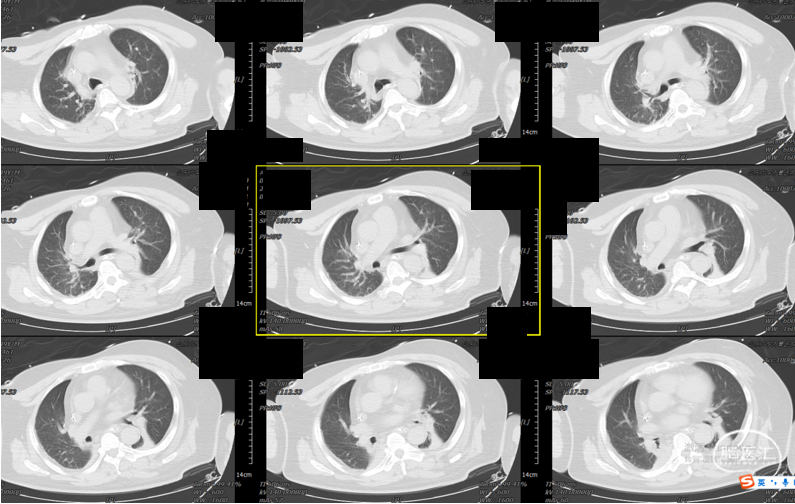

辅助检查:头胸部CT平扫2026-03-14我院脑出血并破入脑室,请结合临床复查,蛛网膜下腔出血。双肺少许纤维灶,双肺坠积性改变,请结合临床隔期复查,双肺少许小结节,考虑低危结节可能,建议结合临床年度随诊复查双肺部分小叶间隔增厚,肺水肿不除外,建议结合临床短期复查,冠脉壁钙化灶,胆囊结石。头颈部CTA2026-03-14我院颅内动脉轻度粥样硬化性改变,左侧优势型椎动脉,椎基底动脉迂曲延长。